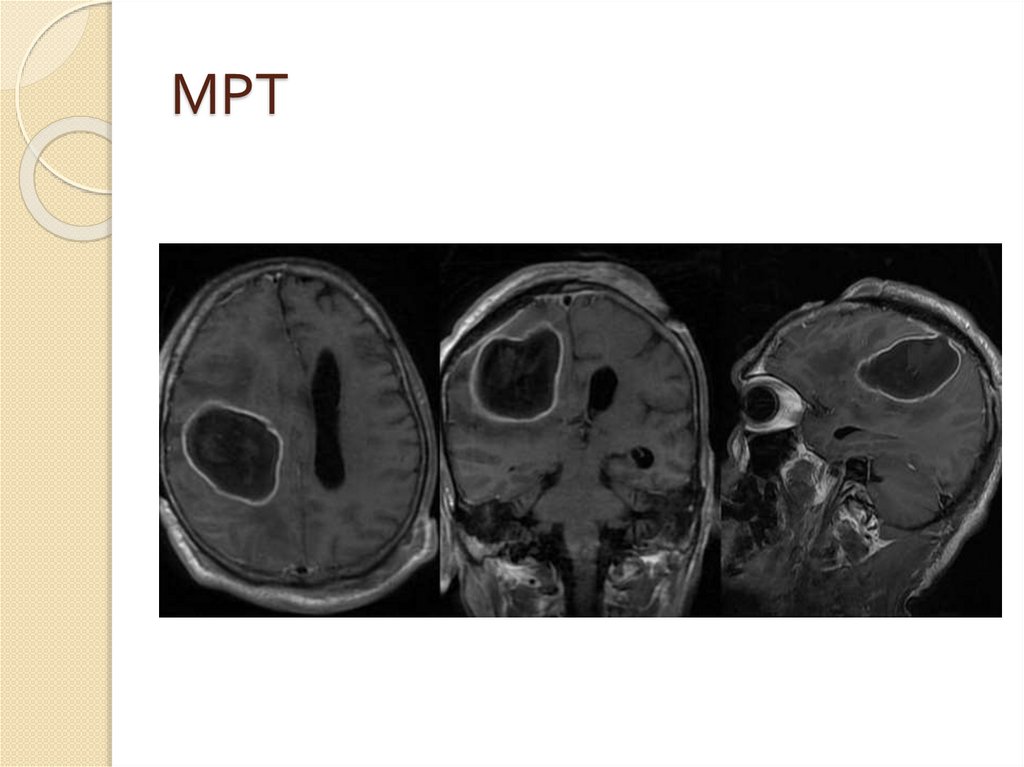

МРТ

30. МРТ